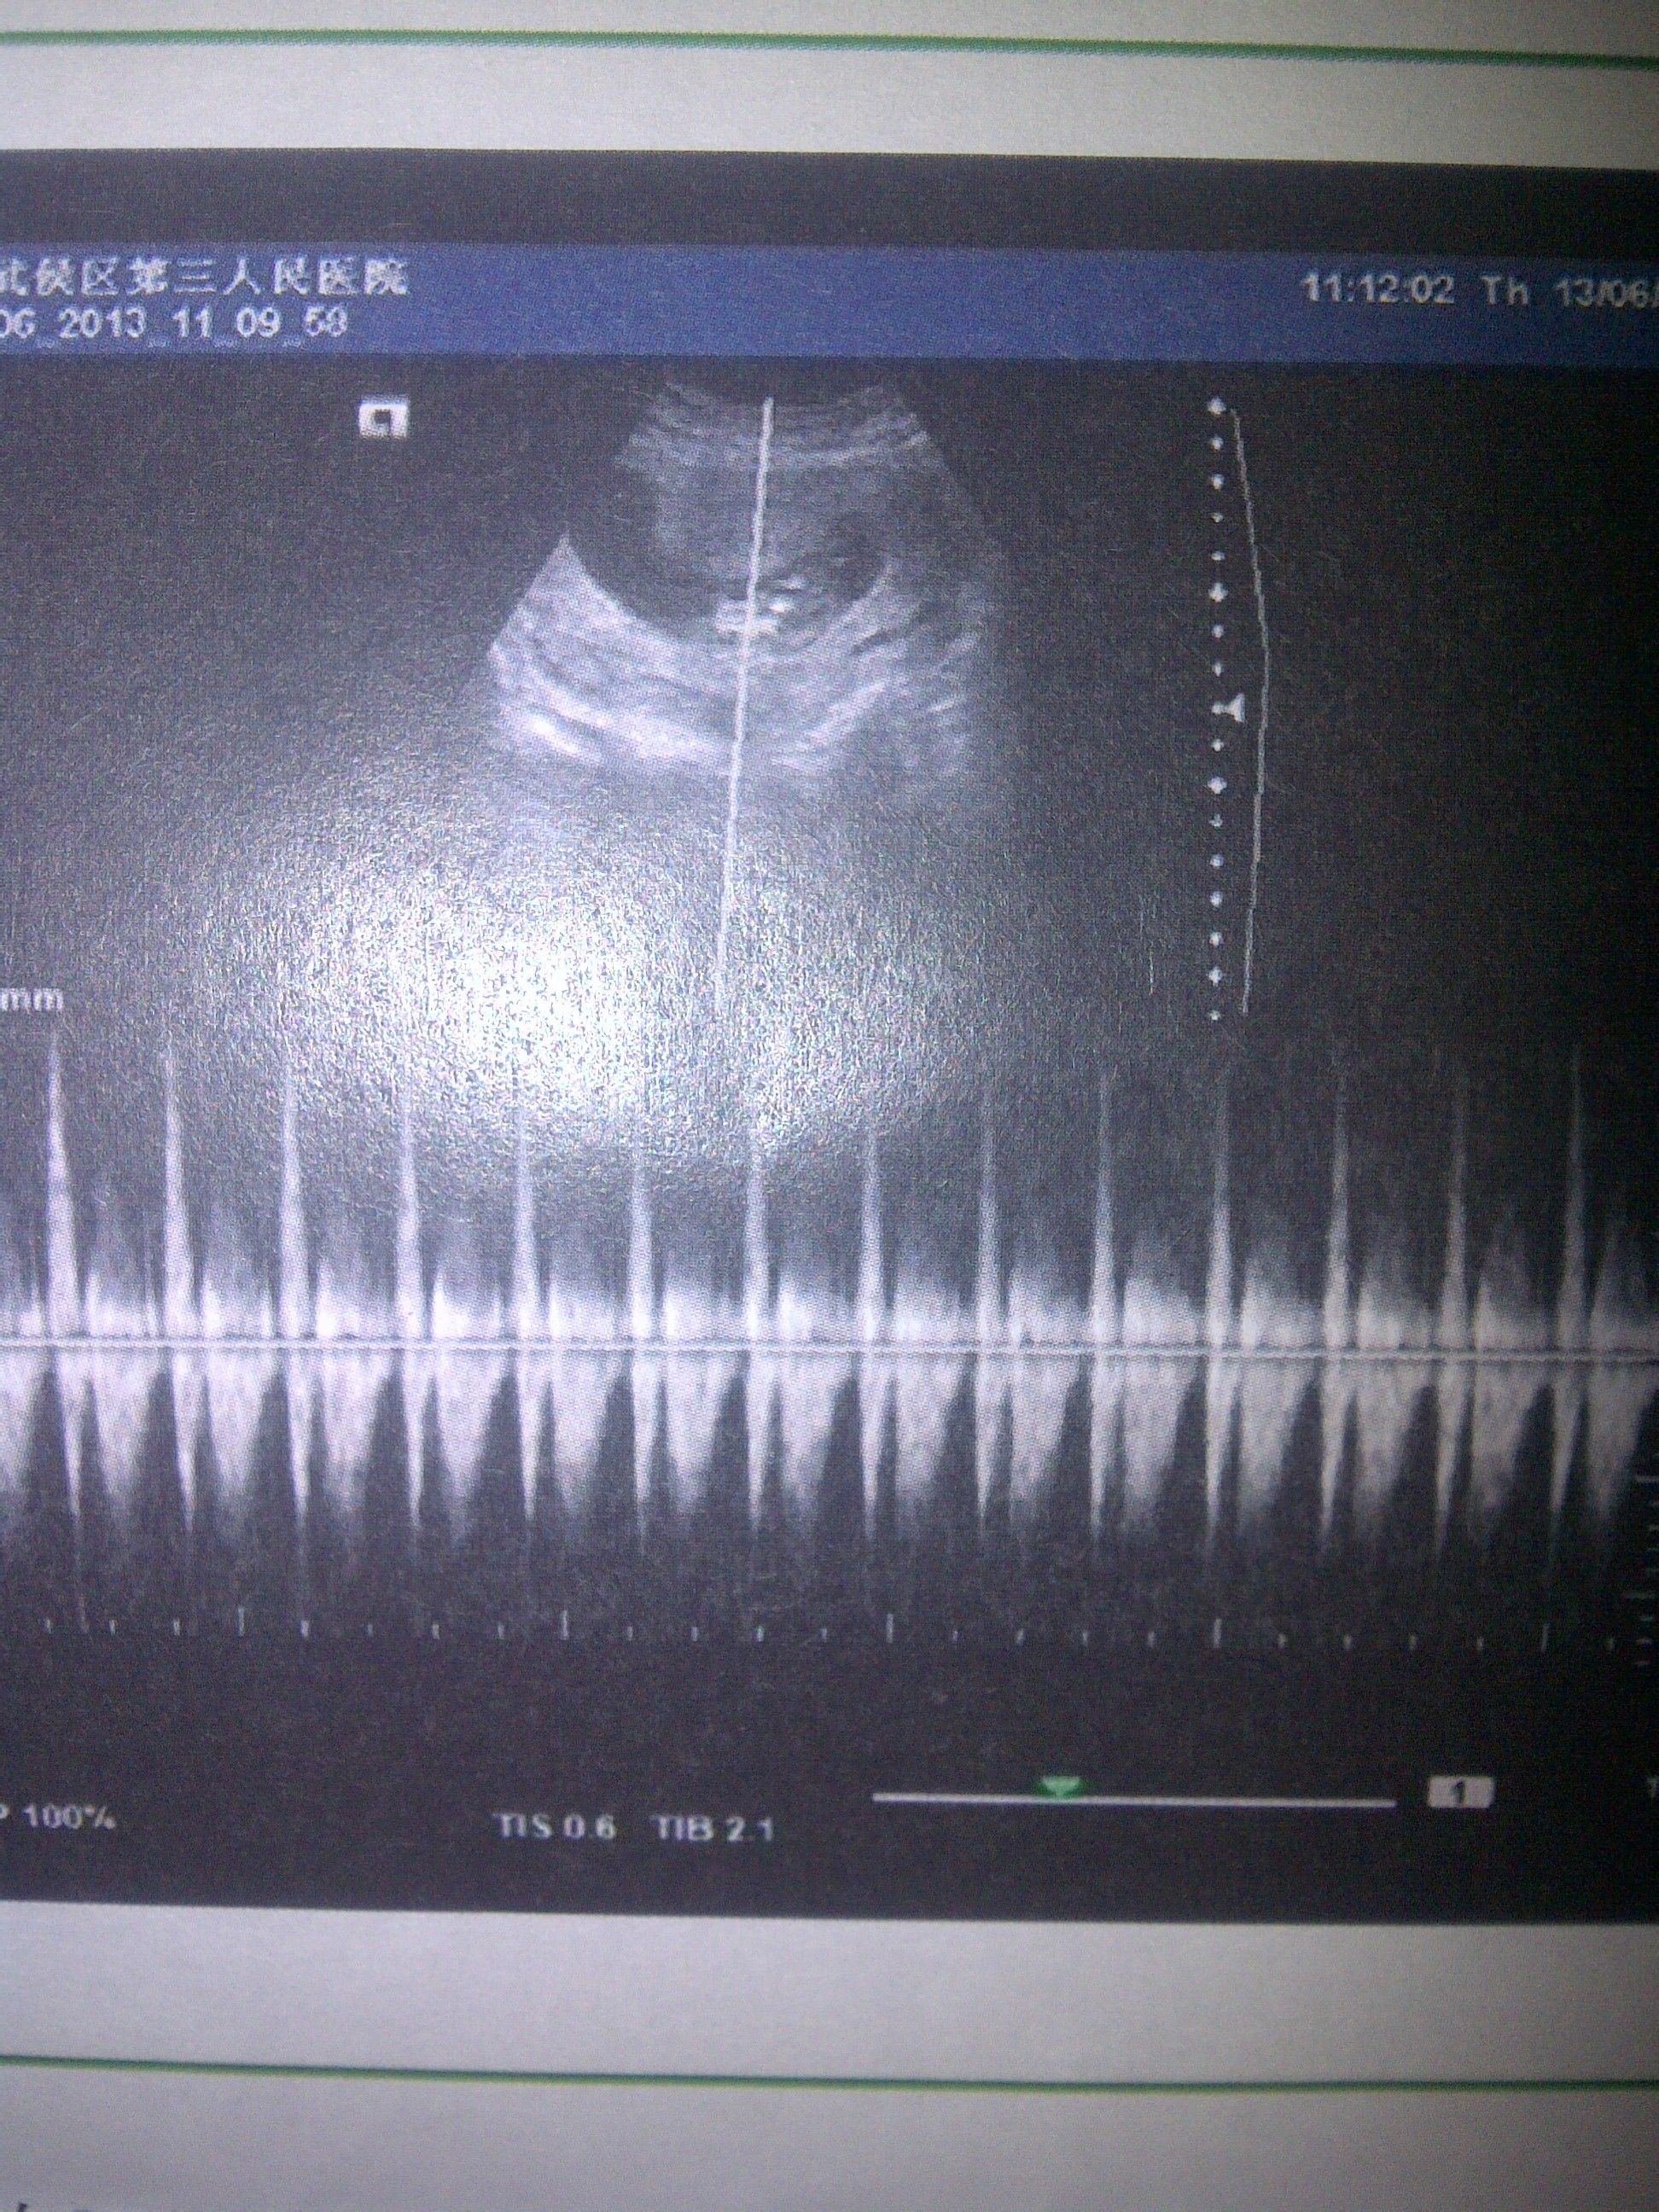

请姐妹们帮我看看,这是我怀孕两个半月照的b超,孩子是好的吗?怎么那么长啊? 点击展开 匿名用户 2013-06-14 16:49 为您推荐: 其他回答 现在是头大身小;我们哪个儿科学上面看着就象外星人一样的 匿名用户 2013-06-15 13:42 不会啊,孩子长的很好啊,要注意身体哦,孩子都这么大了。 匿名用户 2013-06-14 17:36 可以去你拍片子的医院问下相关的医生, 匿名用户 2013-06-14 16:57 相关问题 怀孕7周,如果满3个月b超孩子长的慢怎么办 怀孕七个半月,孩子才四斤 请问这正常吗?是不是有点小?还有50天,能长几斤? 我家这边比较穷,怀孕13周了,都没有去产检过,村里有个诊所,听说可以做B超,这样可以看出孩子的健康